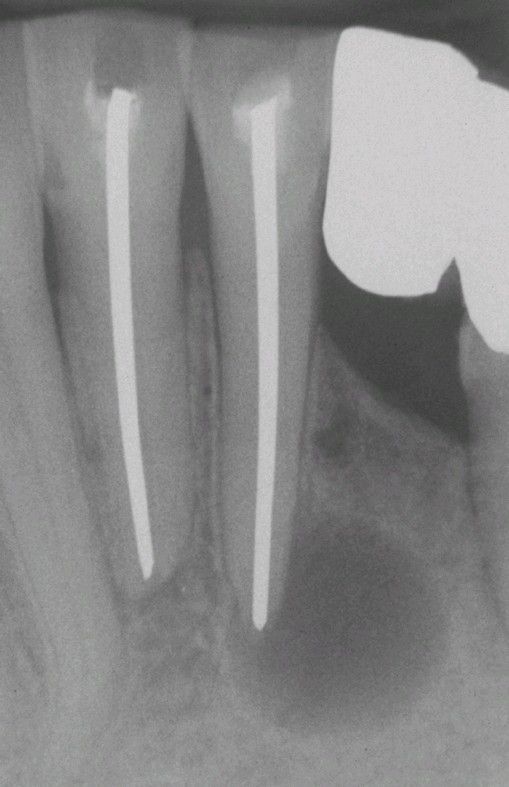

Periapical Cyst

. Well-circumscribed radiolucency intimately associated with the apex of the mandibular central incisor. Note the loss of lamina dura in the area of the lesion.